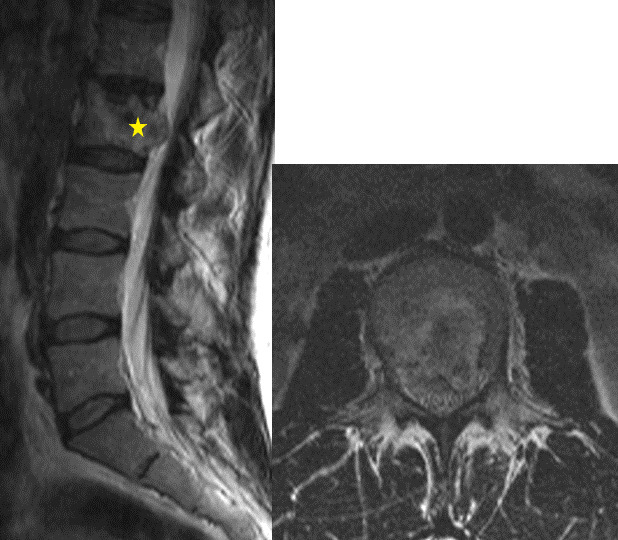

Clinical case: A 40-year-old woman diagnosed with low-grade spinal chondrosarcoma underwent a total en-bloc spondylenctomy (TES) surgery. This technique required a wide resection, anterior reconstruction with a titanium mesh cage (TMC), and posterior stabilization. For several years a favorable clinical outcome was achieved. After 10 years of follow-up, the patient developed acute non-traumatic low back pain without neurological repercussions. The images confirmed a rupture of the titanium cage. After ruling out tumor recurrence, the patient went through spinal instrumentation revision.

Conclusion: Isolated TMC rupture is a rare event scarcely reported in the literature. There is a strong recommendation to instrument two levels proximal and distal to the bone defect in 360° reconstructions after a TES. Stability had likely been lost over the years due to the slow resorption of the bone graft. We consider necessary studies with a higher casuistry and level of evidence to analyze the contributing factors for the event of TMC rupture.